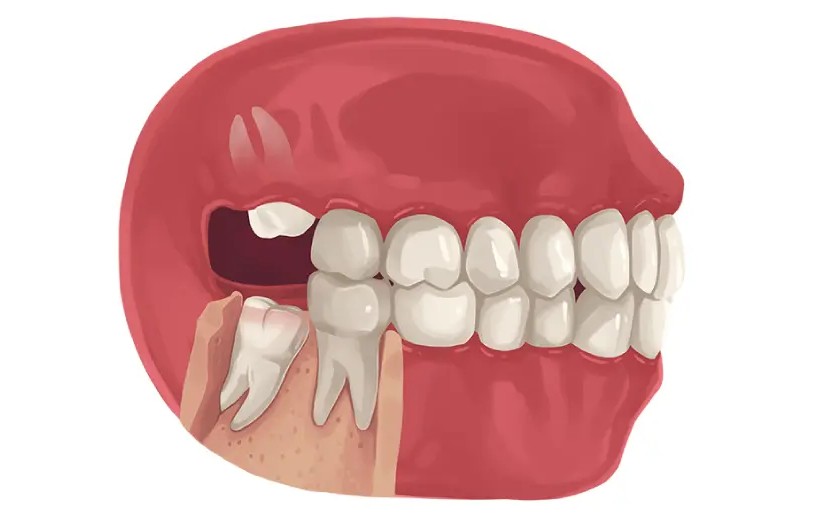

Không giống như các răng khác, răng khôn thường mọc khi hàm đã không còn đủ chỗ, dẫn đến tình trạng mọc lệch, mọc ngầm hoặc mọc kẹt trong nướu. Điều này có thể gây đau nhức, viêm nhiễm hoặc ảnh hưởng đến răng bên cạnh.

- Một số trường hợp răng khôn có chân đâm ngang hoặc mọc chen vào răng số 7, có thể gây đau nhức hoặc làm xô lệch răng.